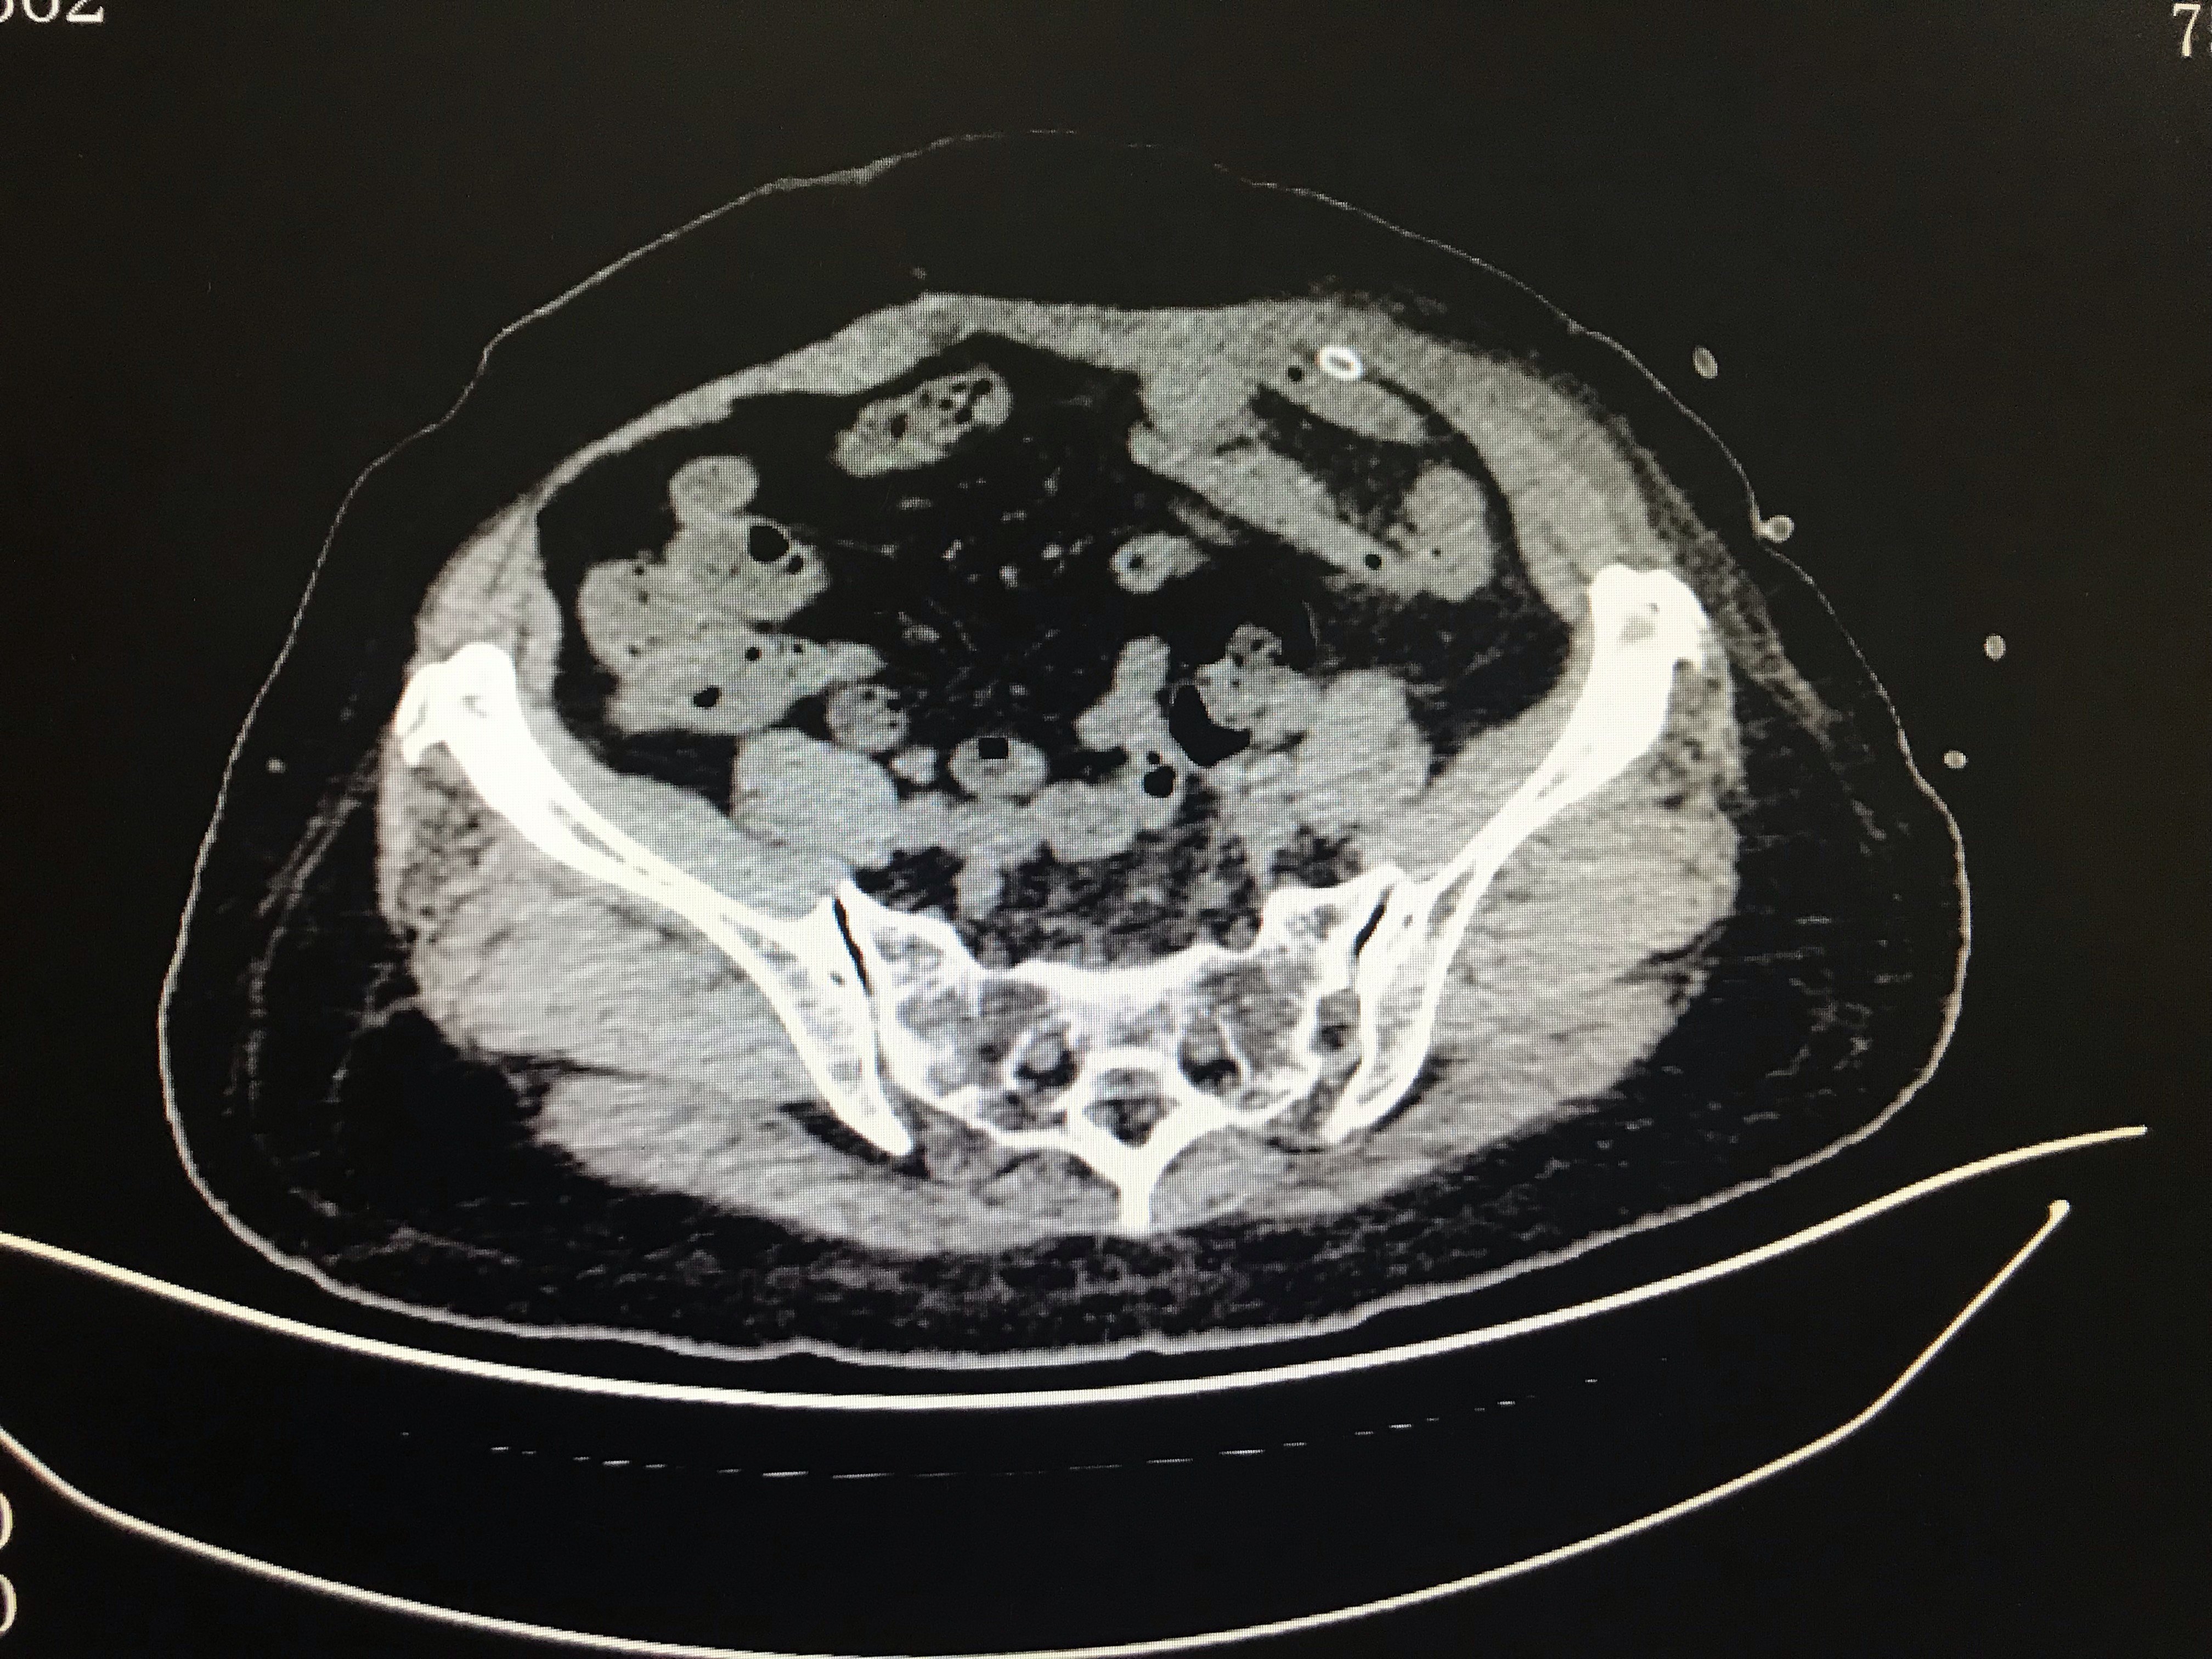

腹壁切口疝超声图片,切口疝图片

腹壁疝(体表 超声图)

切口疝图片

腹壁切口疝图片

切口疝图片腹部

腹部手术切口疝图片